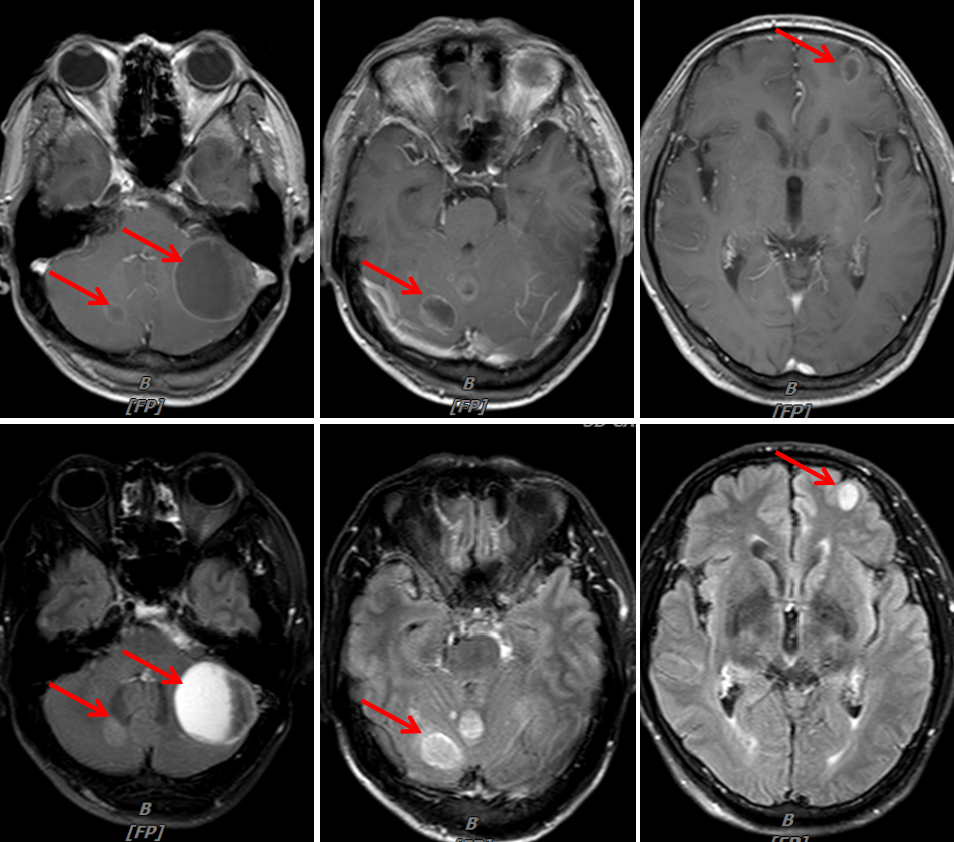

头颈MRI(我院):1.结合病史,脑多发转移瘤;2.筛窦炎。

图4:2020年1月30日,治疗前头颅MRI

图7:2020年3月25日,联合治疗2周期后头颅MRI

图9:2020年5月6日,联合治疗4周期后头颅MRI

图11:2020年6月24日,联合治疗6周期后头颅MRI

病例二总结

本例患者为“左肺上叶小细胞癌(广泛期,cT3N1M1,IV期),伴左肺门淋巴结转移、多发脑转移”,考虑予以免疫联合化疗。为明确并监测患者可能出现的毒副反应,先予以患者1周期EP方案化疗,同时予以全脑放疗1个月。患者未出现明显不良反应,予以患者加用替雷利珠单抗免疫治疗2周期,疗效评价即达到PR,治疗6周期后疗效达到CR。随访至今PFS已超过7个月,疗效持续CR,安全性良好,患者可以耐受。